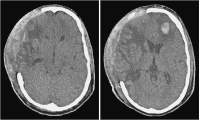

Therapie

Abbildung 2: Eine begleitende thrombozytenfunktionshemmende medikamentöse Therapie erschwert wesentlich alle möglichen neurochirurgischen Maßnahmen (Entlastungskraniektomie, Hirndrucksondenimplantation) und geht mit einem erheblichen Blutungsrisiko einher. Extradural stellt im Besonderen die große Wundfläche mit diffuser Blutungsneigung an der Innenfläche des Hautlappens ein Problem dar. Subgaleale Hämatome nach osteoklastischer Trepanation wirken sich unmittelbar epidural raumfordernd aus. Saugdrainagen können wegen der bestehenden Duraeröffnung nicht eingesetzt werden. Der Temporalmuskel ist in vielen Fällen diffus blutig imbibiert und raumfordernd geschwollen. Insgesamt kann dadurch der dekompressive Effekt der Operation reduziert werden (a). Intradural ist im Speziellen die Hirnpunktion zur Implantation von Parenchymsonden zur Hirndruckmessung problematisch und kann in seltenen Fällen zu Parenchymblutungen führen (b).